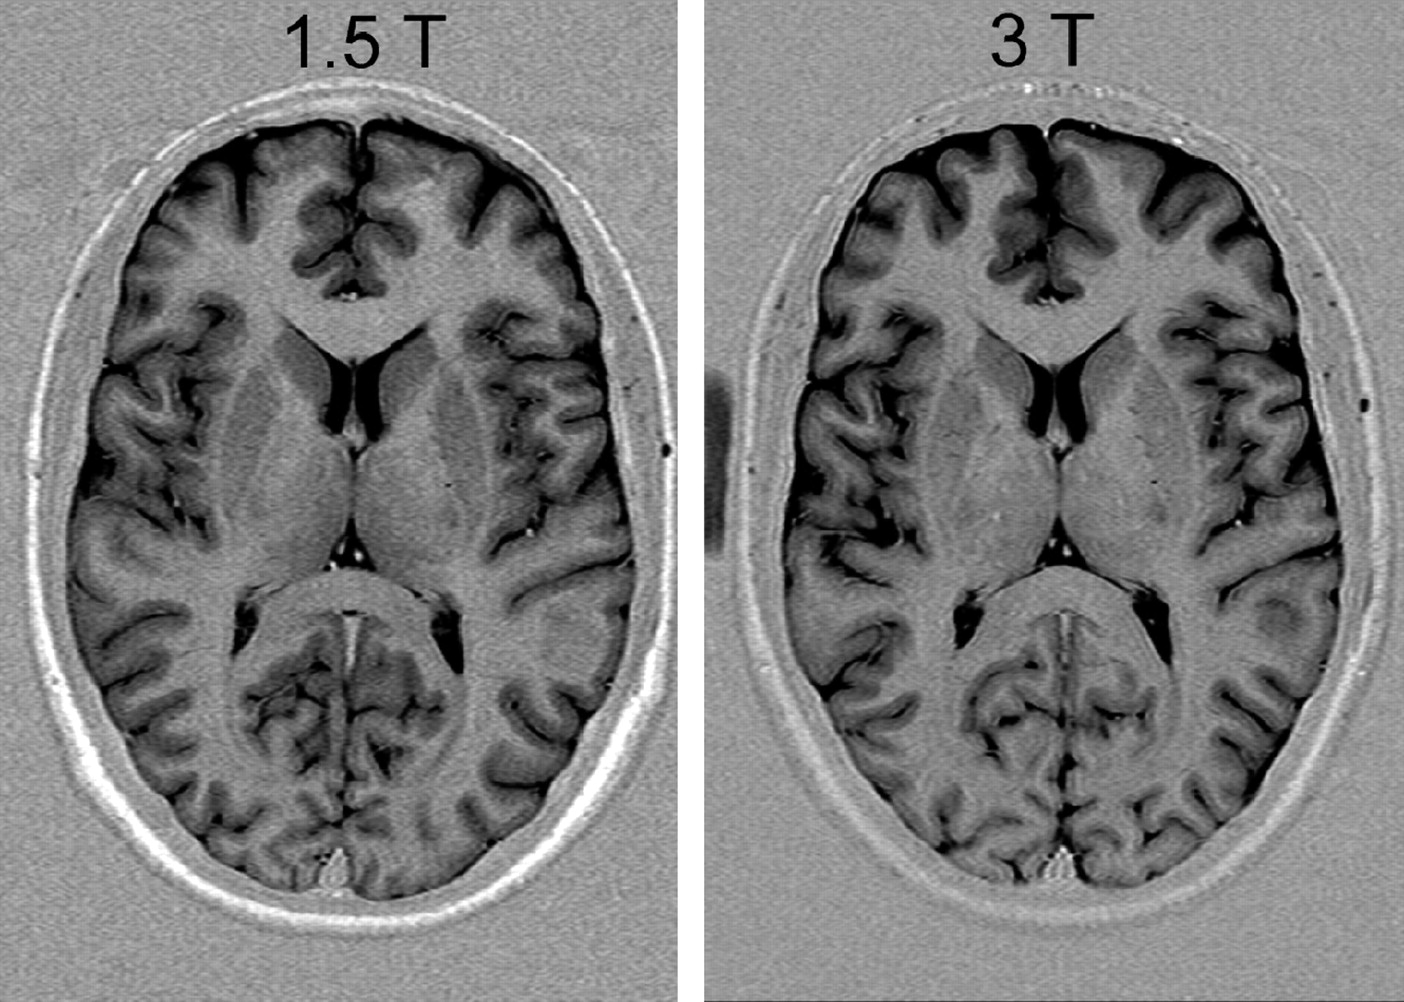

Apparently, gray-to-white matter contrast is reduced in spin-echo T1 imaging at 3T (30) when compared with 1.5T (Fig 6). There are several factors contributing to this observation. T1 times of gray and white matter lengthen and converge at higher fields (31–33). Moreover, shielding effects induced by eddy currents prevent central parts of the image from being properly excited (16), which results in reduced signal intensity of the basal ganglia region. In addition, magnetization transfer effects are enhanced at higher B0, thus reducing signal intensity and contrast. There are several ways to compensate for these effects. For example, inversion recovery sequences appear very well suited if one is only interested in increasing gray to white matter contrast (Fig 7). The inversion pulse, however, interferes with visualization of contrast enhancement following gadolinium administration. Enhancing lesions may not be visible (Fig 8), because in inversion recovery sequences, unlike conventional T1 spin-echo sequences, the tissue with the shortest T1 does not necessarily exhibit the brightest signal intensity, depending on T1. Therefore, inversion recovery sequences are not quite useful for comparative pre- and postcontrast T1 spin-echo imaging, regardless of B0. A different approach to increase gray-to-white matter contrast during T1-weighted spin-echo imaging at both field strengths is to reduce the excitation flip angle (34). Although this reduces SNR slightly, the gain in gray-to-white matter contrast is obvious and more pronounced at 3T (Fig 9). The effect can be predicted from theoretical calculations (35) by using known T1 and T2 relaxation times of gray and white matter (33) but is empirically larger than the theoretical predictions at 3T, probably because of shielding and magnetization transfer effects (34).

Turbo inversion recovery (TIR) sequence at 1.5T (left: TR, 8770 ms; TE, 92 ms; TI, 300; matrix, 512 × 256; section thickness, 3 mm; FOV, 220 × 220 mm2; bandwidth, 130 Hz/pixel) and 3T (right: TR, 8890 ms; TE, 95 ms; TI, 300; all other parameters equal), which demonstrates clear depiction of gray and white matter at both field strengths.